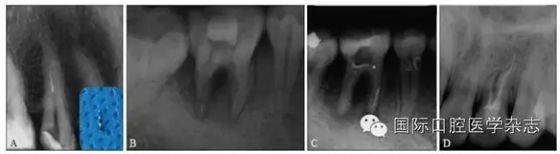

目前,對于分離器械周圍牙本質(zhì)厚度的評估以及取出后殘余牙本質(zhì)厚度的預(yù)測主要需借助影像學(xué)檢查,例如根尖片、錐形束CT(cone beamcomputed tomography,CBCT)圖像等。傳統(tǒng)的平行投照的根尖片無法反映三維立體結(jié)構(gòu),且往往存在解剖結(jié)構(gòu)影像的重疊,不利于臨床判斷,具有一定的局限性。多位學(xué)者[10]的研究表明:平行投照的根尖片會高估實(shí)際的牙本質(zhì)壁的厚度。一些學(xué)者[11-12]的研究表明:當(dāng)分離器械位于上頜第一磨牙近中根管時,采用成角投照(21°)的拍攝技術(shù)與平行投照技術(shù)得到的X線片相比,能更準(zhǔn)確地評估牙本質(zhì)的厚度,為分離器械取出與否提供指導(dǎo)(圖4)。近年來,CBCT在牙髓病學(xué)中的應(yīng)用越來越廣泛,由于CBCT能清楚地反映牙及牙根周圍組織的三維立體結(jié)構(gòu),為牙本質(zhì)厚度的評估與預(yù)測提供了可行性(圖5);因此,CBCT在器械分離的病例術(shù)前風(fēng)險評估方面具有較好的應(yīng)用前景。

A、B:采用平行投照技術(shù)獲得的圖像,模擬取出分離器械后殘余牙本質(zhì)的厚度,分離器械分別位于根管口下3 mm和5 mm;C、D:采用成角投照技術(shù)獲得的圖像,模擬取出分離器械后殘余牙本質(zhì)的厚度,分離器械分別位于根管口下3 mm和5 mm。

圖 4 平行投照與成角投照拍攝技術(shù)對牙本質(zhì)厚度的評估